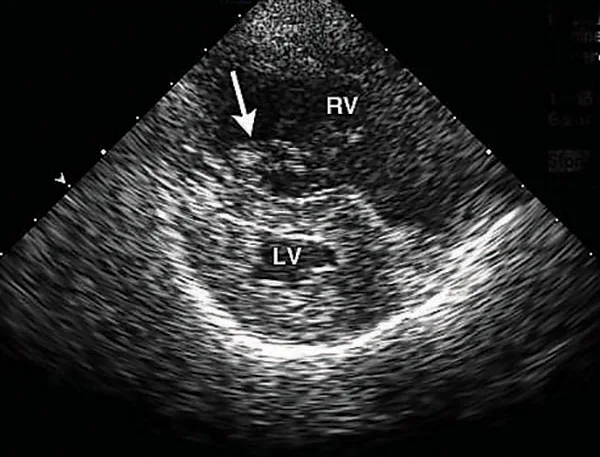

Thoracic radiograph of dog with lung and cardiac changes due to severe heartworm disease.

Radiograph from a dog with severe heartworm disease illustrating severe pulmonary arterial dilation, right heart enlargement, diffuse bronchointerstitial infiltrate, and focal region of pulmonary consolidation from embolized heartworms

Radiographs before (A) and 11 days after (B) melarsomine injection showing increased overall pulmonary infiltrate with focal region of pulmonary consolidation from embolized worms (black arrow). A progressive increase in cranial pulmonary artery size can be seen (gray arrow). Images courtesy of Clarke E. Atkins, DVM, DACVIM